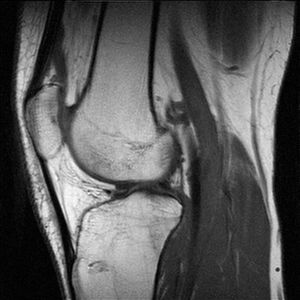

تصوير بالرنين المغناطيسي

تصوير رنين مغناطيسي إنگليزية: Magnetic resonance imaging (MRI) هي وسيلة تصوير طبي لتوضيح التغييرات الباثولوجية في الأنسجة الحية و للرنين المغناطيسي أستخدمات غير طبية ومن الناحية الفيزيائية فهي تعتمد على ما يسمى بالرنين المغناطيسي النووي RMN . يعتبر التصوير بالرنين المغناطيسي من الفحوص المكلفة وغير متوفرة بشكل دائم في كثير من المستشفيات، وهناك صعوبات عند عمل هذا النوع من الأشعة عند المرضى الذين يخافون من الأماكن المغلقة أو المرضى الذين يشتكون من البدانة المفرطة.

للرنين المغناطيسي أستخدمات تشخيصية متعددة لأنه قادر و بدقة عالية على تصوير الأنسجة الداخلية دون التركيز على العظام مما يساعد على تشخيص الأورام خبيثة أو حميدة التي تنبع من الأنسجة